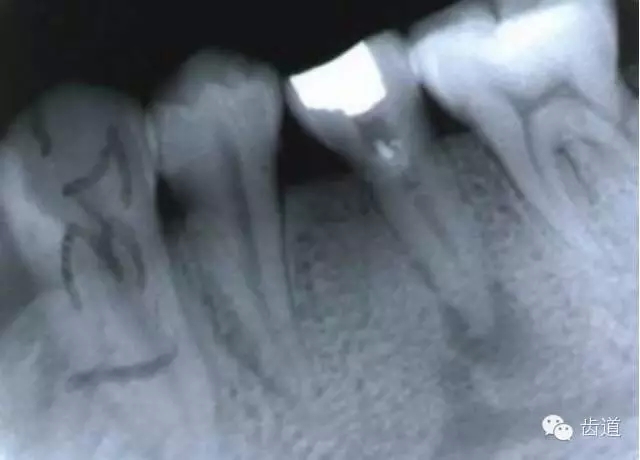

左上7近中頰根器械折斷

右上6腭根器械折斷